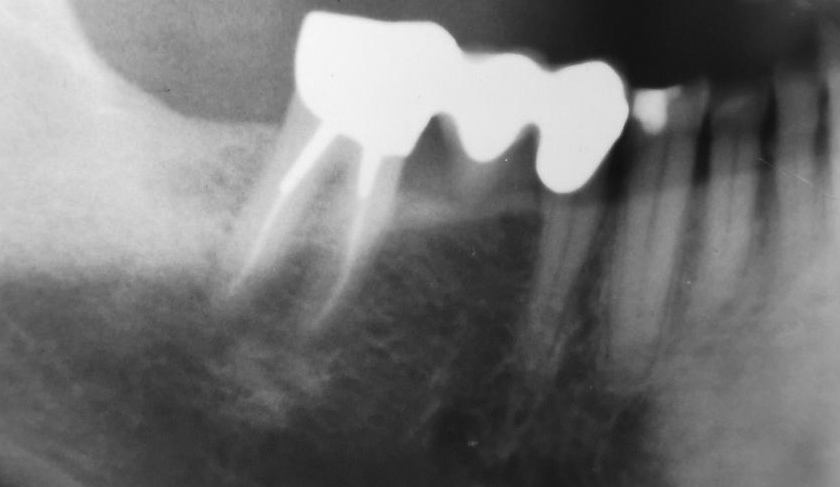

Die Implantate wurden primärstabil und mit der angerauten Oberfläche bis auf Knochenniveau inseriert. Die Röntgenkontrolle belegt eine ausreichende Länge der eingesetzten Implantate BioniQ® Plus.

Die Röntgenaufnahme 14 Monate später belegt ein stabiles, distal des 2,9er Implantats möglicherweise zugenommenes, periimplantäres Knochenniveau.